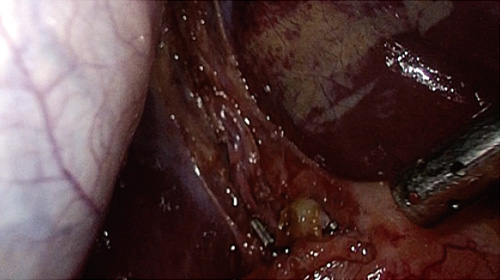

さまざまな医療映像を高精細・高画質で細部までクリアに映し出せる本機は、高い精度が求められる手術や検査時の視認性向上に貢献します。

本シリーズは、4K(3840×2160ピクセル)の高解像度LCDパネルとMini LEDバックライトを搭載しています。細かいエリアでの明暗調整が可能になり視認性が向上することに加え、バックライトに独自のローカルディミング(部分駆動)技術「Backlight Master Drive」を用いて、高いピーク輝度(LMD-27M1MD:2,250cd/m2、LMD-32M1MD:1,850cd/m2、LMD-43M1MD:2,000cd/m2)と100万:1の高コントラスト比を実現しています。

HLG(Hybrid Log-Gamma)及びPQ (Perceptual Quantization)準拠の信号を入力し、色調調整メニューでガンマをHLGもしくはPQに設定することで、HDR信号の明部と暗部の再現性を細部まで向上させた表現が可能になります。また、4Kの放送規格であるITU-R BT.2020に準拠した広色域に対応しています。

モニター前面に内蔵した明るさセンサーが手術室内の照明環境を検知して、モニターの明るさを自動的に調整します。手術中にICG*を使用するなど、暗い照明へ変化するケースでも視認性を確保することができます。